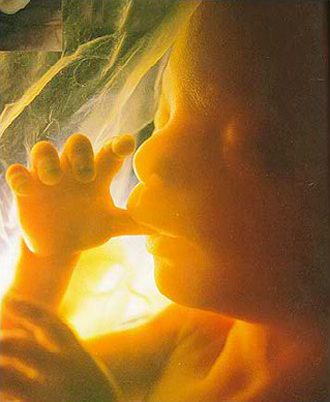

- 4차원 후기 정밀 초음파 (26~28주)